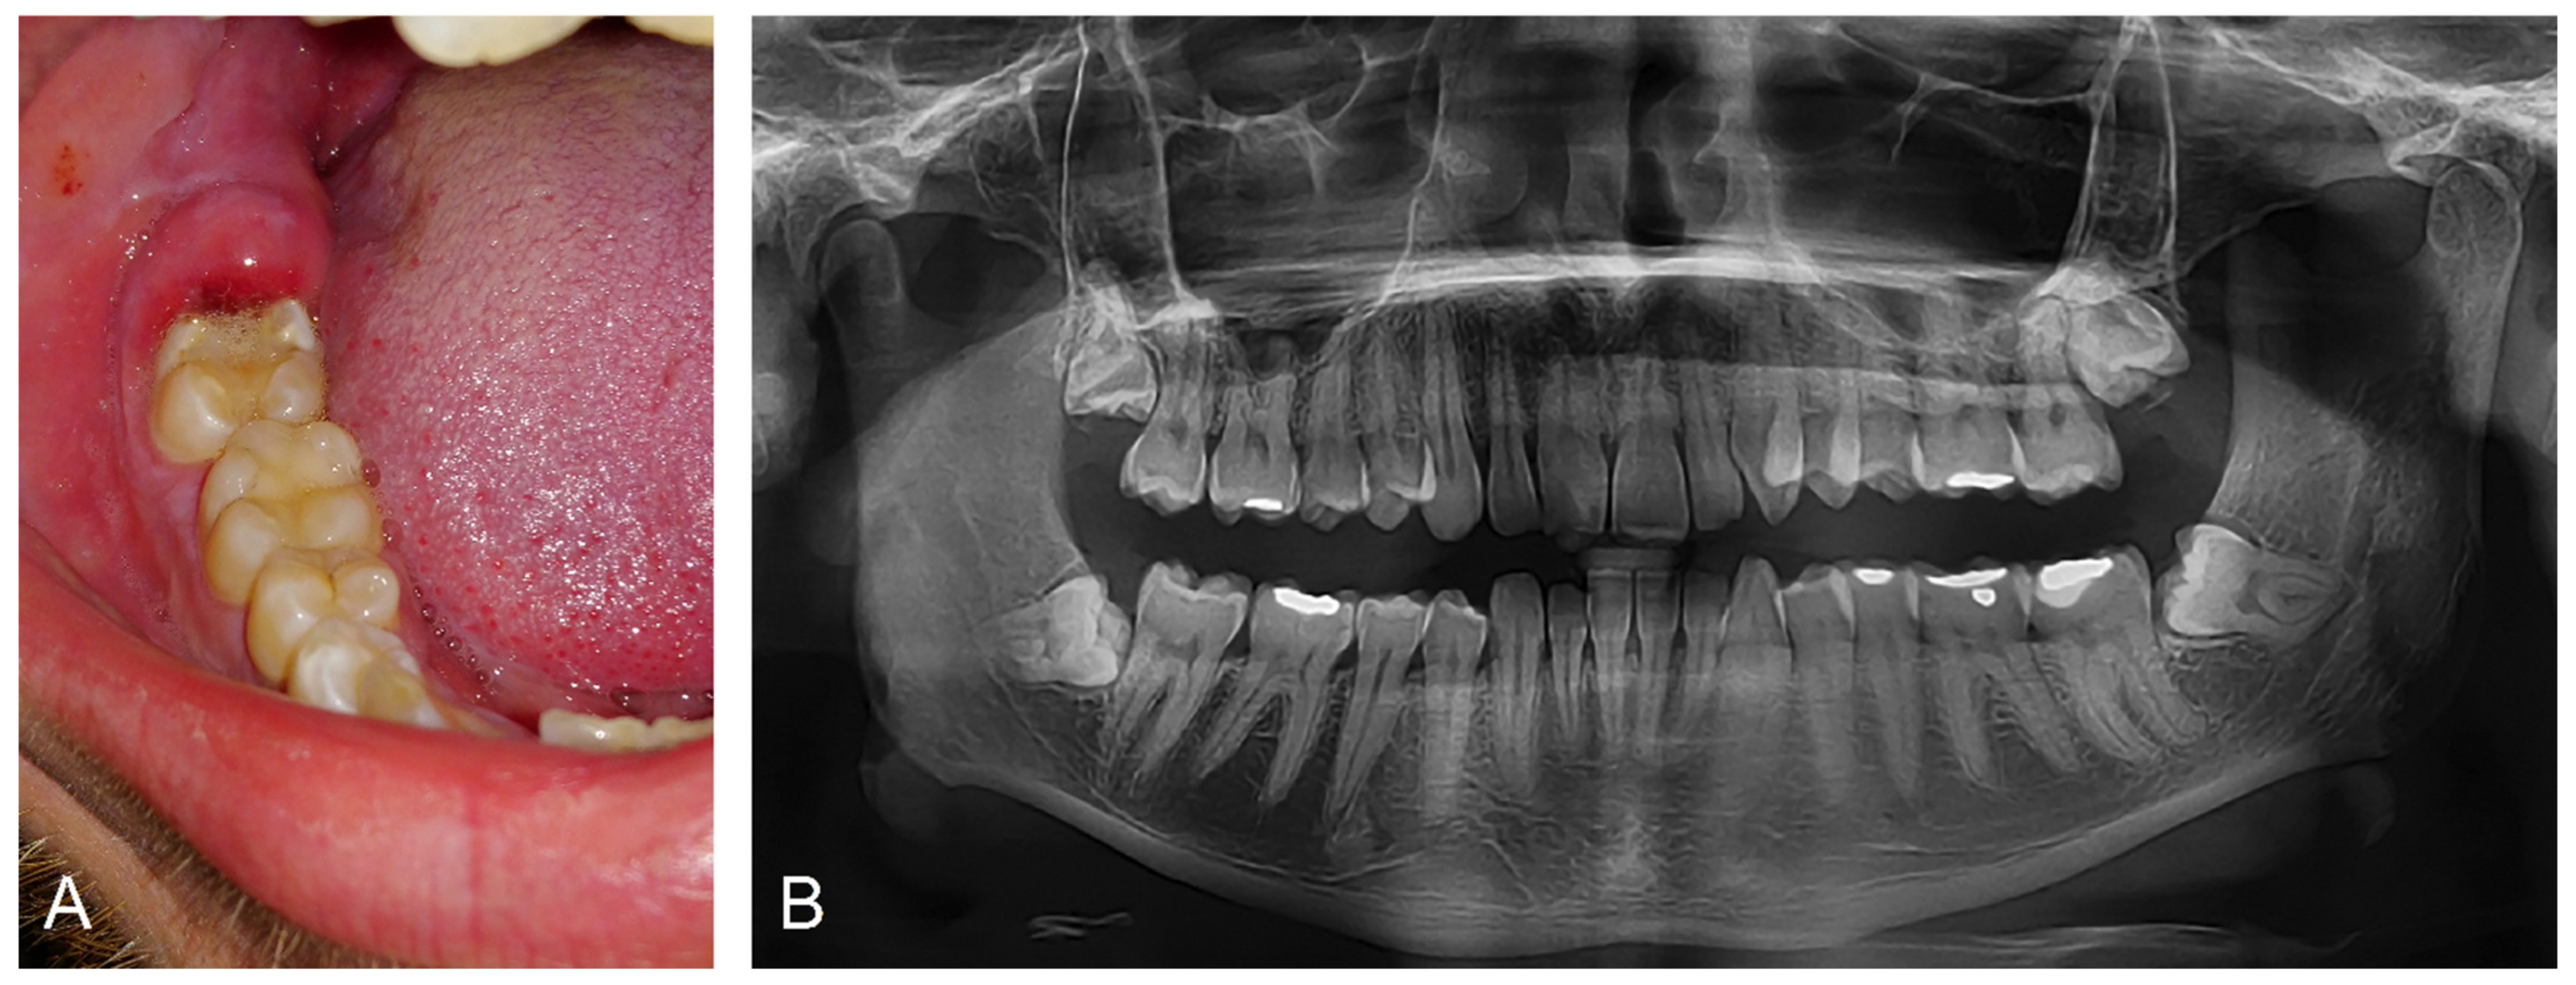

Pericoronitis manifests with the expression of inflammation signs—pain, redness, swelling, heat, and loss of function. Pain begins locally and is limited to the soft tissues around the erupting tooth. Patients usually describe it as pulsating and eventually radiating to the surrounding tissues and/or distant areas (soft palate, mouth floor, retromandibular and submandibular space, throat, ear, or temporomandibular joint) [38]. It usually worsens over time and becomes more accentuated under pressure on the affected area. Pain may also disturb sleep, and its exacerbation during mastication may limit food intake. During the clinical examination, swollen, reddened soft tissue above and around a tooth is found (Figure 4).

Figure 4.

Clinical manifestation of pericoronitis and panoramic radiograph. Image (A) demonstrates inflamed soft tissues covering incompletely erupted right lower third molar. Image (B) displays a preoperative panoramic radiograph of the same patient demonstrating incompletely erupted third molars.

The magnitude of the edema and pain may prevent the patient from reaching the resting position of the mandible and force him/her to keep it in a depressed position. Traumatization or even ulceration of the soft tissues as well as purulent exudation may be observed. Tissue and detritus decomposition may cause malodorous breath (halitosis), bad taste, or changes in taste perception [39]. Regional submandibular and neck lymphadenopathy is usually unilateral. Bilateral lymphadenopathy, pyrexia, palatoglossal arch asymmetry, facial asymmetry, malaise, difficulty swallowing (dysphagia), or restriction in mouth opening, which may be accompanied by pain (trismus) are warning marks indicating a more severe course that may include infection spread to the adjacent tissue spaces, i.e., the deep spaces of head and neck [38,40].